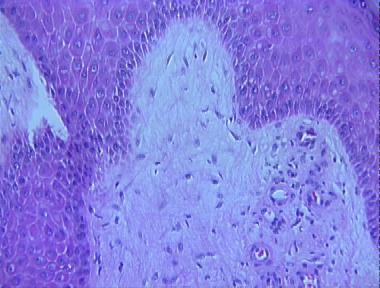

chronic lymphedema

Histologic Features